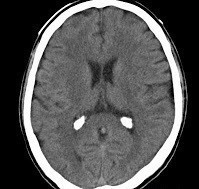

Question 1: Une imagerie cérébrale est également réalisée aux urgences dont voici une coupe :

L’imagerie cérébrale réalisée en urgence correspond à une tomodensitométrie cérébrale sans injection de produit de contraste iodée en coupe axiale.

L’hyperdensité intra-ventriculaire correspond à une banale calcification des plexus choroïdes classique pour l’âge.

L’imagerie ne retrouve donc aucune anomalie pouvant expliquer la symptomatologie présentée par le patient.